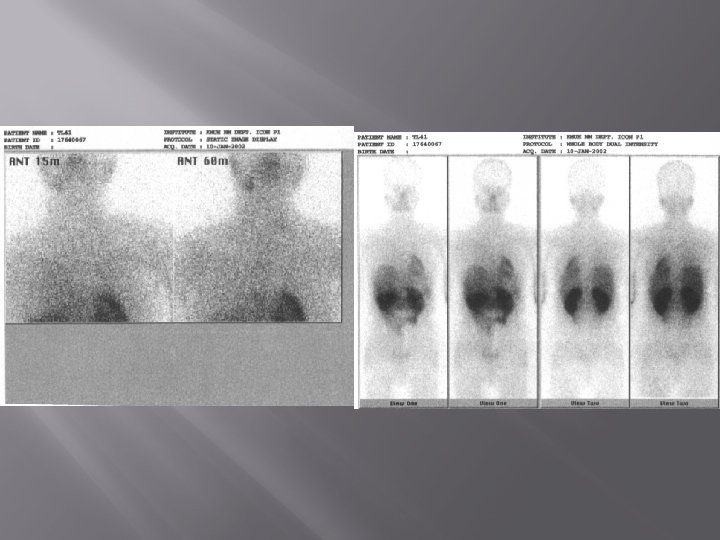

RADIOIODINE THERAPY Thyroid remnant Before ablated Thyroid remnant After ablated

I-131 TB SCAN 24 H AFTER TX

1. Laki-laki 48 th post operasi total thyroidectomy karena malignansi thyroid. Sisa kelenjar thyroid yg sakit yang masih ada pada thyroid scan dengan TC-99 m 2. THYROID SCANN PRE RADIASI DAN POST RADIASI